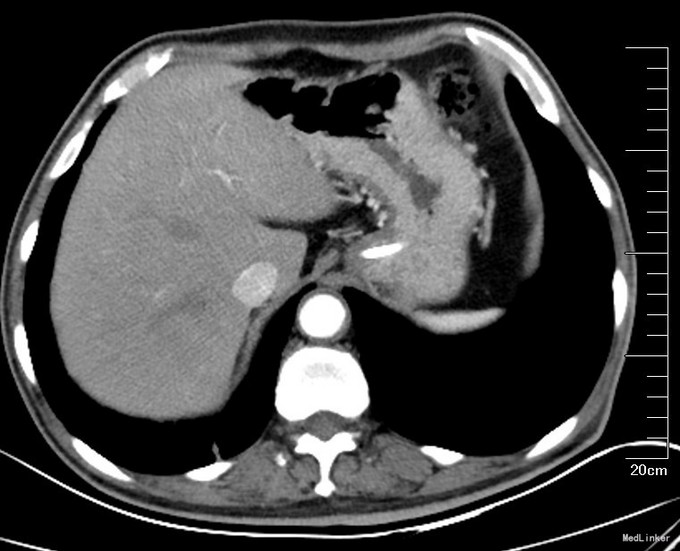

入院后,复查全腹增强CT(图3,图4):结节较前缩小。胃壁增厚。肠癌系列正常。行PET-CT:1、原右肾门水平十二指肠前方FDG高代谢软组织影区域本次扫描代谢未见显著增高,符合治疗后改变。2、右肺上叶多发磨玻璃影,FDG代谢略高,注意重度不典型增生,3、胃窦远端FDG代谢略升高,目前考虑炎症可能大,需密切结合镜下及病理;十二指肠管壁增厚伴周围多发渗出,炎性改变可能大。胃镜:窦前壁近幽门管可见一溃疡性病变,大小约1.5*2.0cm,表面白苔,周围粘膜充血水肿。幽门口变形,收缩舒张不良。十二指肠球部粘膜充血,球后黏膜光滑、色泽正常。此次病理:胃溃疡性病变,局部腺体轻度非典型增生,幽门螺杆菌阴性。上消化道造影(图5):胃窦部变形,胃壁略僵硬。 考虑患者胃窦部病变不能除外恶性。同时肺内病灶不能除外恶性。考虑为肿瘤的复发及远隔转移,手术治疗效果不佳,予以口服化疗药物治疗。空肠营养管建议终身携带,帮助增强营养,如患者不耐受,可以改为内镜下经胃造瘘空肠营养管(PEJ)。随访。